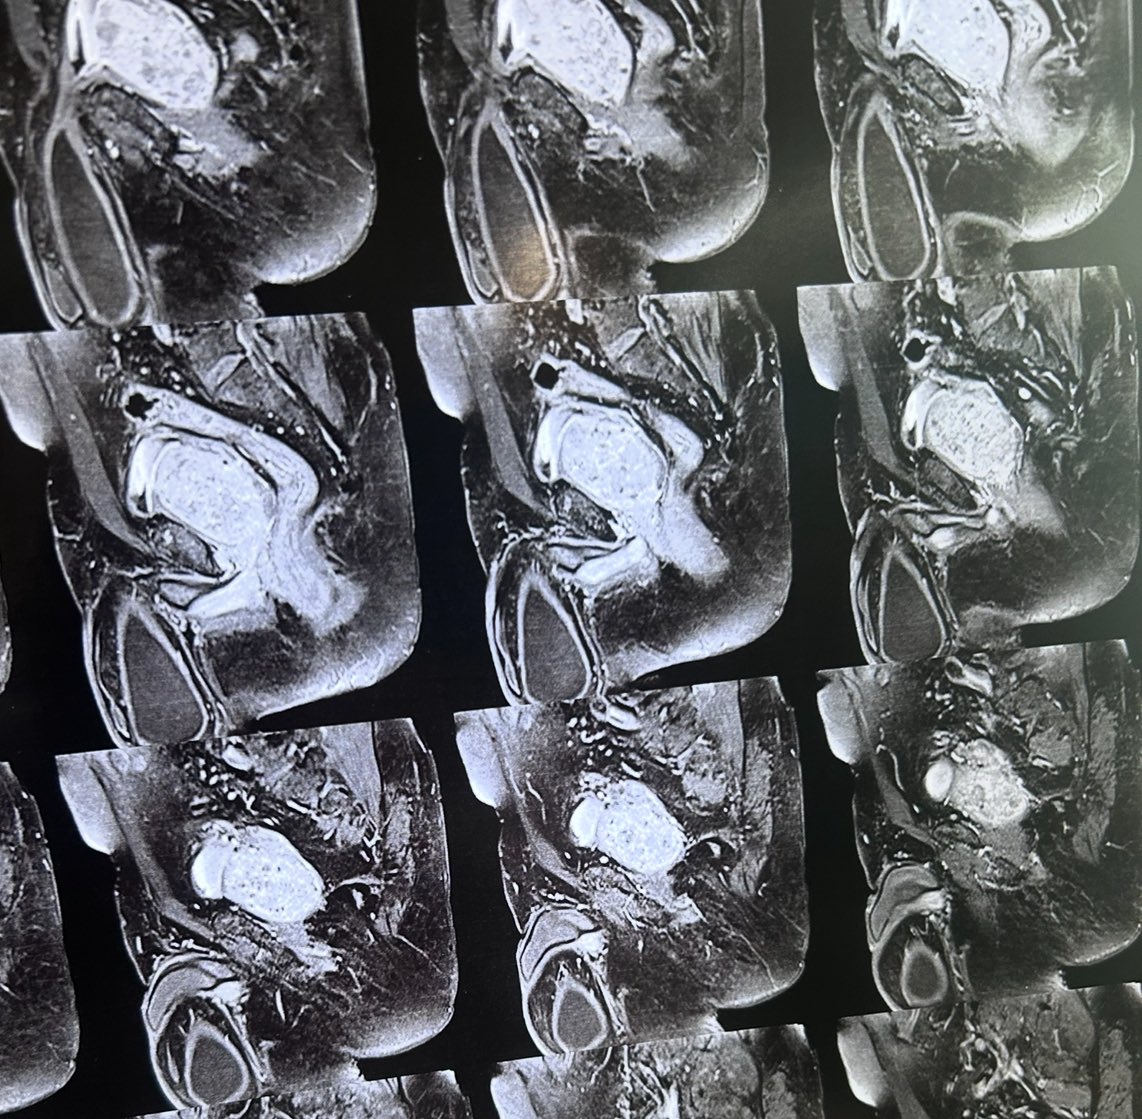

Winning the battle without bullets. Retroperitoneal fibrosis improved dramatically after 6 months of prednisolone and tamoxifen

6

8

72